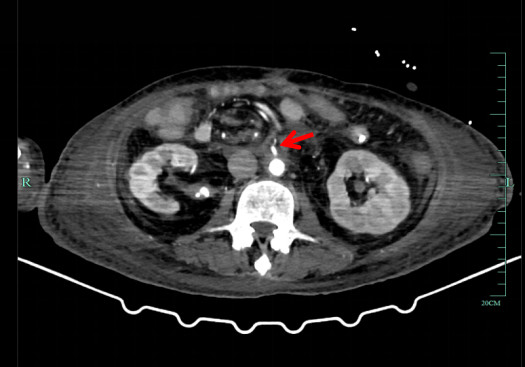

患者二次移植术后感染风险高,术后予美罗培南1 g /8 h静滴、更昔洛韦250 mg/12 h静滴、复方磺胺甲噁唑片0.48 g BIW鼻饲、万古霉素500 mg /8 h静滴、伏立康唑200 mg /12 h微泵维持和卡泊芬净50 mg /d(首次剂量70 mg)静滴抗感染。结合腹水、静脉血和引流液培养结果及药物浓度调整抗感染方案,结合患者感染指标逐步停用抗感染药物。他克莫司2 mg, 2次/d鼻饲抗排异,根据他克莫司药物浓度调整用量,第1个月为15~20 ng/mL,6个月内为10~15 ng/mL,之后为8~10 ng/mL[6]。第1天免疫球蛋白25 g, 1次/d静滴,继续使用3~5次至他克莫司达到治疗水平。甲泼尼龙降阶梯治疗,护肝护胃化痰肠外营养支持,每周两次肠镜观察移植肠功能,密切关注造口观察窗,监测排异情况。再次移植术后血红蛋白呈下降趋势,存在药物抗凝禁忌,制定非药物血栓防治措施。每日监测凝血功能,10月7日予那屈肝素钙注射液4 100单位QN皮下注射。床边B超动态监测肝脏、肠系膜及双下肢和双上肢血流早期识别血栓生成。地高辛片250μg, 1次/d口服控制房颤,减少血栓诱因[5]。术中采取减少小肠缺血时间等有效的干预措施预防吻合口血栓[7]。9月21日5%葡萄糖氯化钠溶液以15 mL/h鼻饲,9月23百普力以20 mL/h鼻饲,10月15日流质饮食,10月25日半流质饮食并转入结直肠外科病房。术后患者移植肠黏膜红润,移植肠血流通畅(图 3、图 4),肠蠕动可,床边肠镜及病理未见明显异常,11月11日患者病情稳定,顺利转入康复医院继续治疗,随访至3个月未发生免疫排异反应,移植肠功能正常。

| 图 3 患者二次移植后移植肠动脉 |